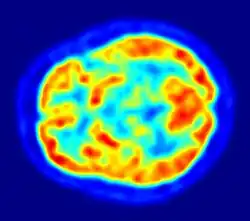

Es handelt sich dabei um eine Variante der Emissionscomputertomographie. PET erzeugt Schnittbilder von lebenden Organismen, indem es die Verteilung einer schwach radioaktiv markierten Substanz (Radiopharmakon) im Organismus sichtbar macht und so biochemische und physiologische Funktionen abbildet (funktionelle Bildgebung). Sie beruht auf der gleichzeitigen Detektion (Aufspüren) zweier Gammastrahlungsphotonen, die nach dem Zerfall eines Positronen emittierenden (aussendenden) Radionuklids entstehen (β+-Zerfall). Die PET wird heute nahezu ausschließlich zusammen mit einer CT oder MRT als Hybridverfahren durchgeführt.

Basierend auf dem Prinzip der Szintigrafie wird dem Patienten zu Beginn einer PET-Untersuchung ein Radiopharmakon verabreicht, meist durch Injektion in eine Armvene. Radiopharmaka sind als Spürsubstanzen verwendete Medikamente, die unterhalb einer physiologisch wirksamen Dosierung eingesetzt werden, und als wesentlichen Bestandteil Radionuklide enthalten, die Positronen emittieren (β+-Strahlung). Die im Körper emittierten Positronen haben nur eine im Bereich von Nanosekunden liegende Lebensdauer und geraten fast unverzögert in eine Wechselwirkung mit einem Elektron. Dabei entsteht eine sekundäre Vernichtungsstrahlung (Annihilation), bei welcher zwei hochenergetische Photonen (Energie je 511 keV) in genau entgegengesetzte Richtungen, also mit einem Winkel von 180 Grad zueinander, ausgesandt werden. Das PET-Gerät enthält viele, meist ringförmig um den Patienten angeordnete Detektoren für die Photonen. Durch eine schnelle Elektronik werden nur solche Zerfallsereignisse gezählt, die auf exakten Koinzidenzen zwischen je zwei gegenüberliegenden Detektoren beruhen. Aus der zeitlichen und räumlichen Verteilung dieser registrierten Zerfallsereignisse wird auf die räumliche Verteilung des Radiopharmakons im Körperinneren geschlossen und eine Serie von Schnittbildern errechnet.

Im Gegensatz zu den auf Transmission basierenden Tomografieverfahren beruht die Bildentstehung bei PET und SPECT auf Emission und bildet somit die Verteilung des zuvor injizierten Radiopharmakons im Körper ab. Daraus ergibt sich eine primär funktionelle Abbildung und erst in zweiter Linie, in Abhängigkeit von der dargestellten Funktion, eine morphologische Abbildung. Deshalb liegt die Bedeutung der Anwendung von PET u. a. in der Beantwortung von Fragestellungen nach Stoffwechselvorgängen (z. B. Glukosestoffwechsel), Rezeptorstatus (z. B. Dopamin-Rezeptoren), oder Oberflächen-Antigen-Eigenschaften (z. B. PSMA-Status). Wichtige, klinische Anwendungen liegen in der Onkologie, Neurologie sowie Kardiologie.